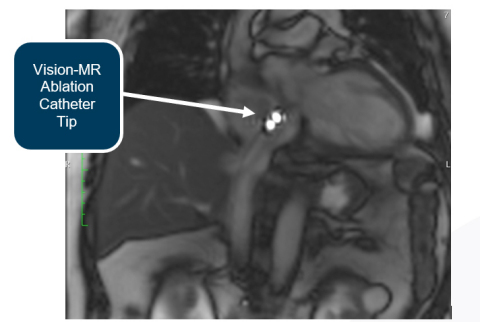

De procedures werden uitgevoerd met gebruikmaking van oorspronkelijke MR-beeldvorming op de Siemens scanner, wat het bedrijf active catheter imaging noemt Met deze beeldvormingstechniek kan men de Vision-MR ablatiekatheter gemakkelijk identificeren zonder gebruik van een actief tracking- of mappingsysteem.

Active catheter imaging is bewezen zeer effectief bij de procedures uitgevoerd bij het hartcentrum in Dresden. Dr. Christopher Piorkowski gaf commentaar tijdens een procedure, “Dit is prachtig. Het is beter dan fluoroscopie. Bij fluoroscopie kan je je de anatomie alleen verbeelden. Hier kun je het zien.”